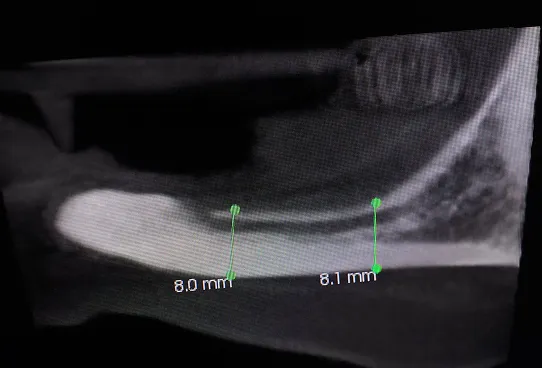

TRANSPOZYCJA NERWÓW ZĘBODOŁOWYCH DOLNYCH – IANT

Ta szczególna metoda używana jest w obszarze dolnego łuku zębowego w sytuacji braku dostatecznej ilości kości na wysokość. Metoda stosowana jest w sytuacji rozległych zaników kostnych w bocznych odcinkach żuchwy, w której wprowadzenie implantów groziłoby uszkodzeniem gałązek nerwowych nerwów zębodołowych dolnych. Gałązki nerwowe biegną wraz z naczyniami krwionoś-nymi we wspólnej pochewce w kanałach kostnych, umieszczonych symetrycznie po obu stronach w trzonach żuchwy.

Technika polega na chirurgicznym ich przemieszczeniu, a przez to stworzeniu bezpiecznego miejsca dla wszczepienia implantów o odpowiednej długości, co gwarantuje ich stabilną pozycję. Stosuje się ją wraz z zabiegiem rekonstrukcji kostnej przy użyciu biomateriałów w formie granulatu i membran.

Zabieg ten stosowany jest rzadko, jako alternatywa rozległych regeneracji kostnych. Wybierany bywa jako alternatywa operacyjna tylko w sytuacji, gdy konwencjonalne metody odbudowy kostnej są niewystarczające lub generują ryzyko braku skutecznej odbudowy kostnej celem wszczepienia implantu.